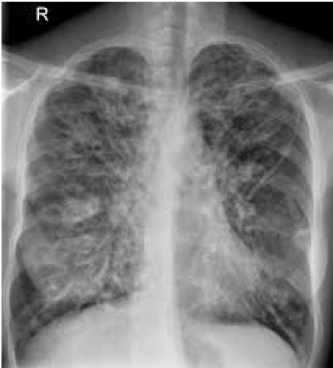

Cystic Fibrosis –> compromised mucosal barrier in lung which leads to recurrent infection